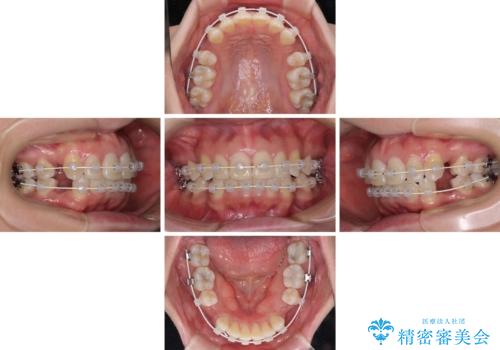

インビザラインが続けられない ワイヤー装置による抜歯矯正

- 上の前歯の飛び出した感じと上下前歯のデコボコを気にして来院された患者様です。

叢生が強く、口元の突出感もあるため、上顎左右第一小臼歯4本を抜歯することとしました。

奥歯の咬み合わせ改善が必要なため、ワイヤー装置による矯正治療を強くお勧めしまたが、本人の希望でインビザラインにて治療を開始することとなりました。

インビザラインでの抜歯治療は予定通りに治療が進まないことが多いため、必要であればワイヤー矯正に切り替えるとお伝えした上で治療を開始しました。

2年ほどインビザラインを使用しましたが、どうしても歯の移動がマウスピースに追随せず、全顎ワイヤー矯正へ切り替えました。

ワイヤー装着後は2年弱で、しっかりと仕上げることができました。